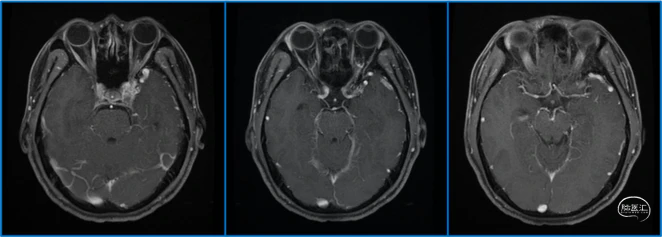

典型病例

蝶顶窦旁DAVF属于Borden III型,需要积极外科治疗。

静脉的引流路径决定患者静脉高压的临床表现,预后风险,治疗方案。